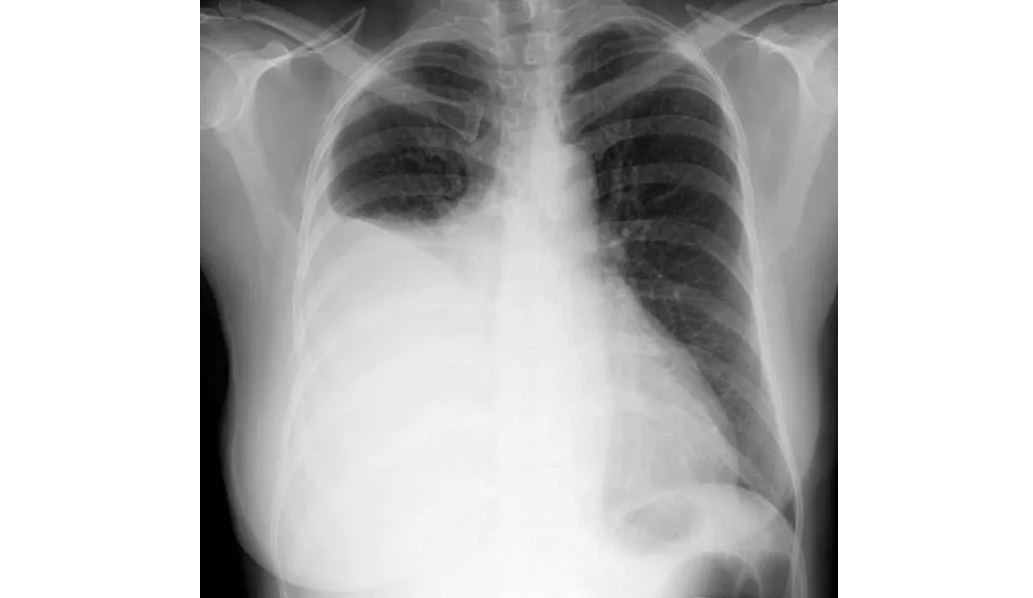

Farmacocinética de los antibióticos en derrames pleurales infectados.

08 julio 2024

En este estudio sobre farmacocinética de antibióticos realizado en pacientes con derrames pleurales infectados se encontró que los antibióticos de uso común, como amoxicilina, metronidazol, piperacilina-tazobactam y clindamicina, alcanzan niveles en el líquido pleural equivalentes a los de la sangre y por encima de la CIM para las bacterias que se sabe que causan infección pleural. La preocupación sobre la penetración de antibióticos de uso común en el espacio pleural infectado (excepto por la trimetroprima)  son infundadas. Thorax, 4 de julio de 2024.